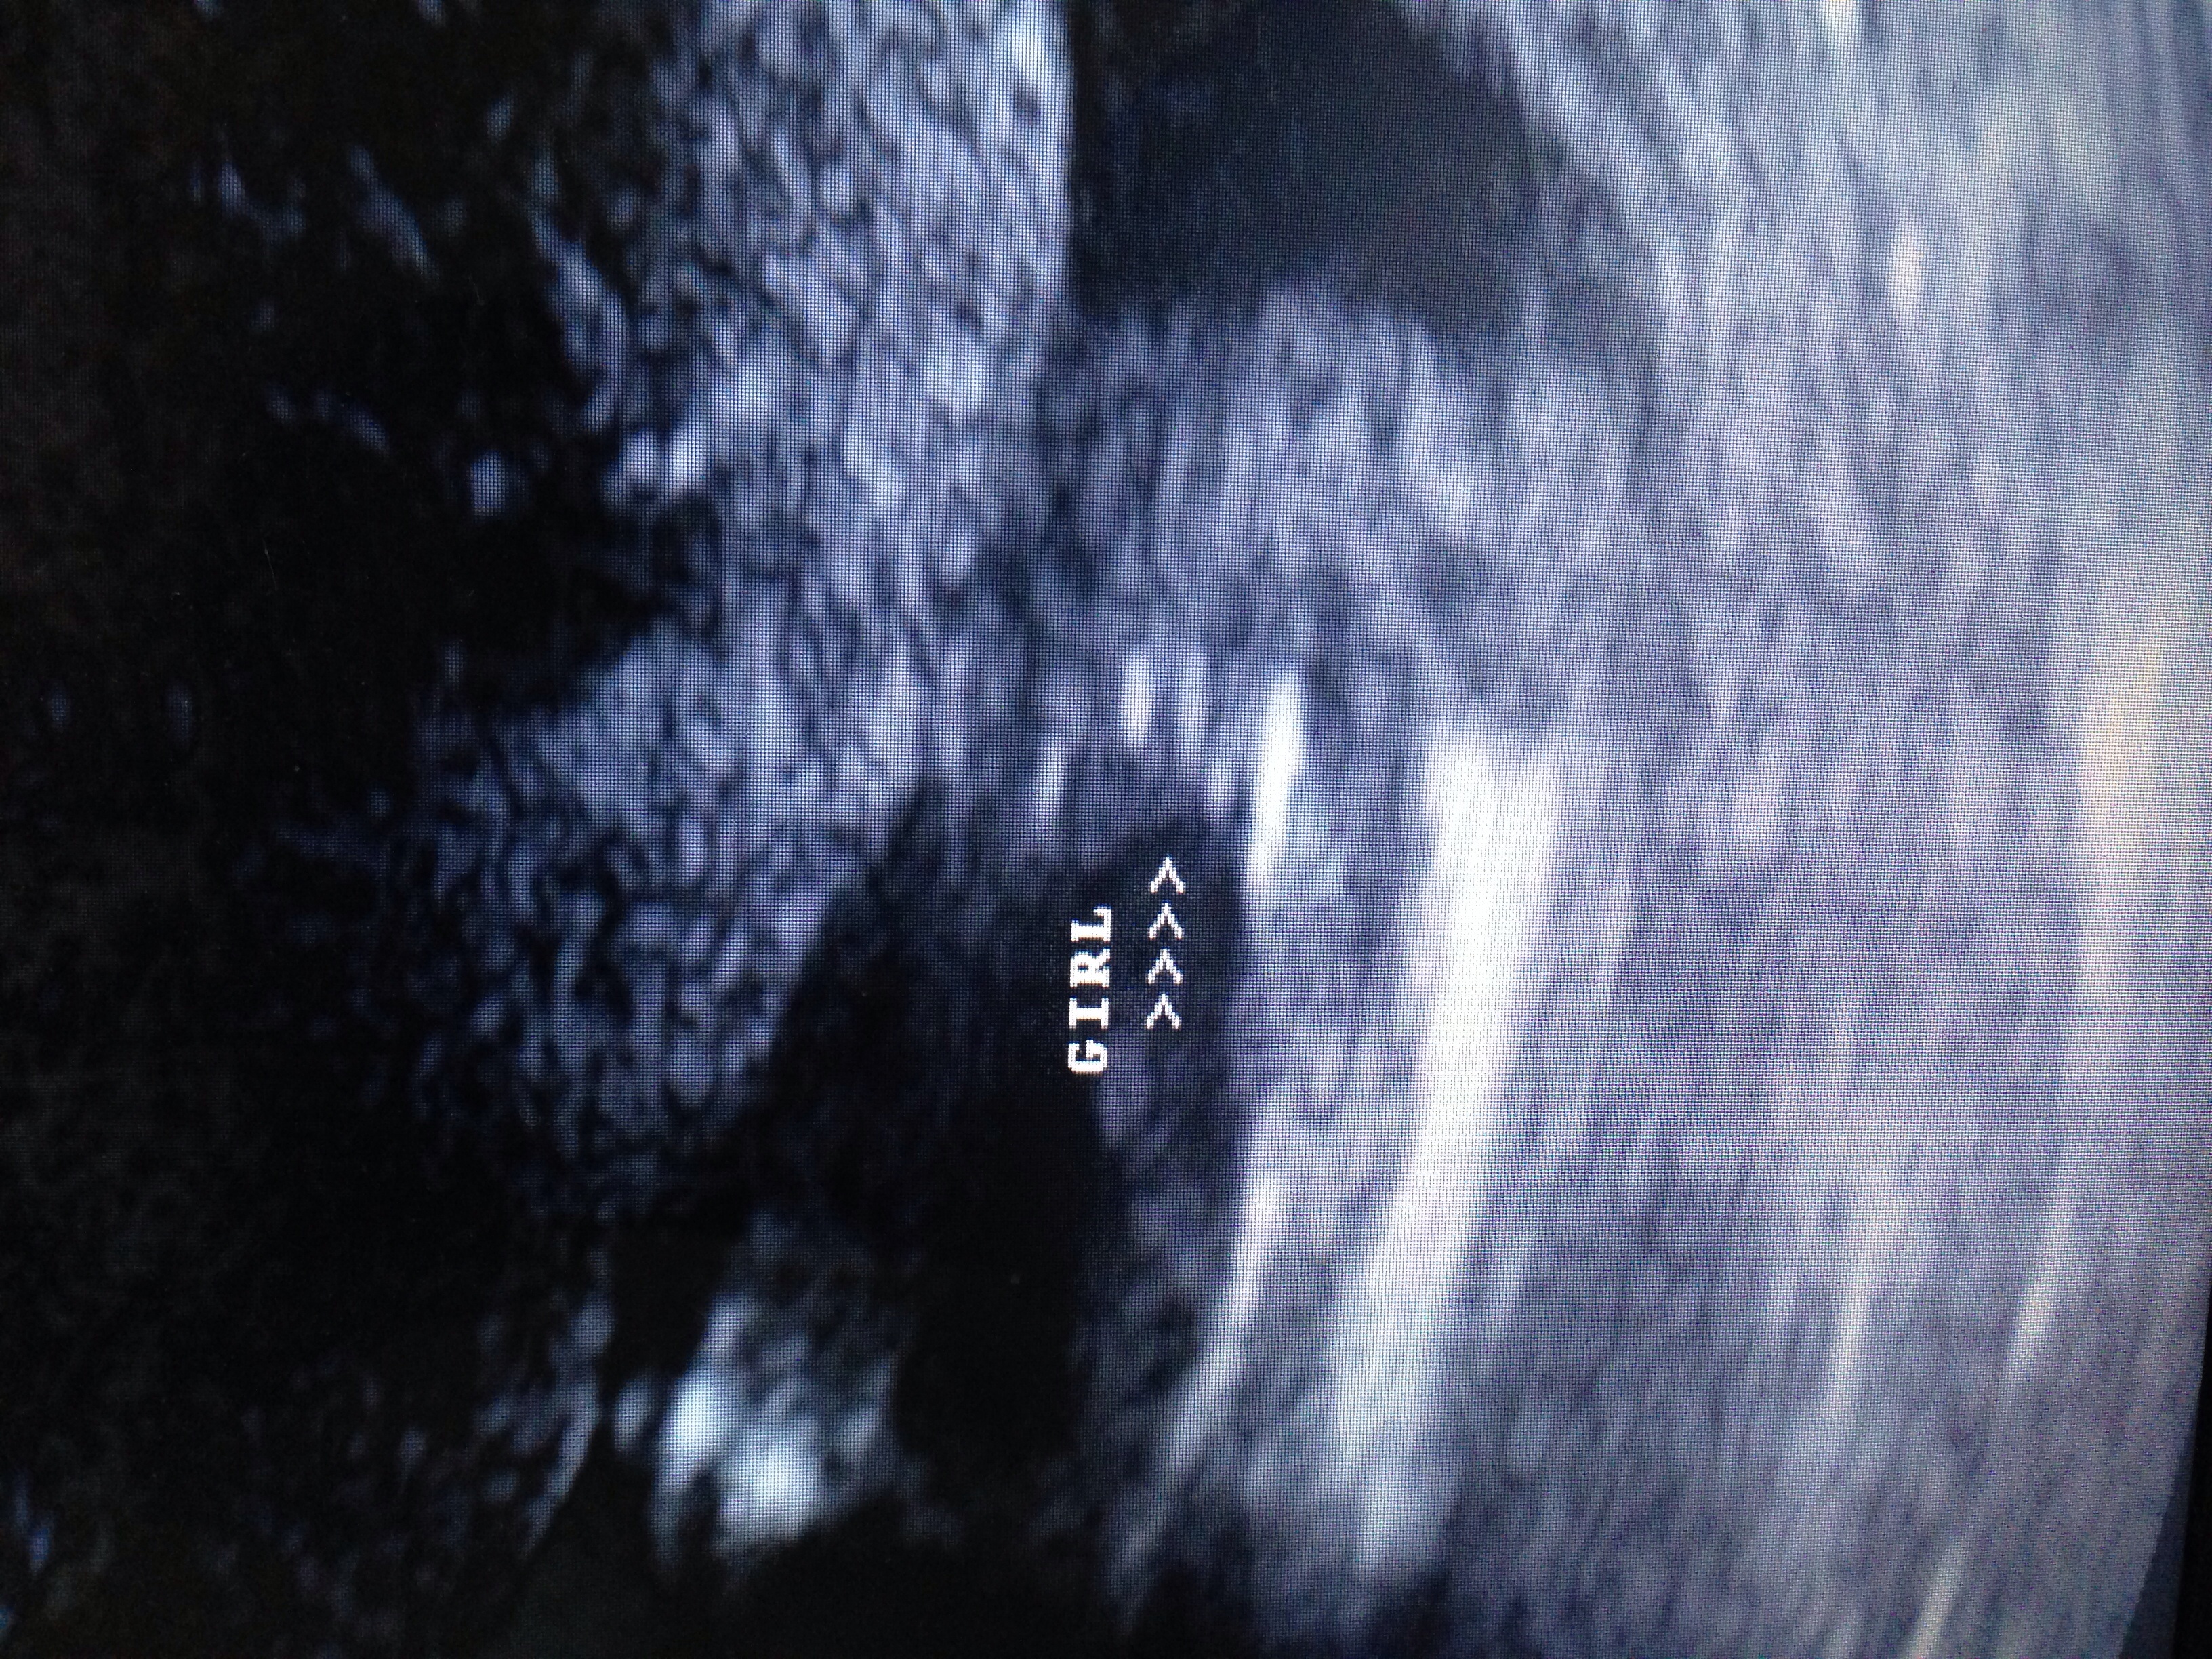

Attachment 17209Attachment 17210These pictures were taken at an elective ultrasound taken at 16 weeks. Baby kept her legs tucked but tech was able to get these 2 shots. Would you go out and buy pink or wait? Thank you in advance.

That looks totally girly to me :princess:

Huge congratulations on your daughter:HH:

Definitely girly, congrats! x

girl congrats

Girl for sure

Yeah, that is a girl. Those are good shots :) Congrats!!

Yep all girl!! Congrats :D